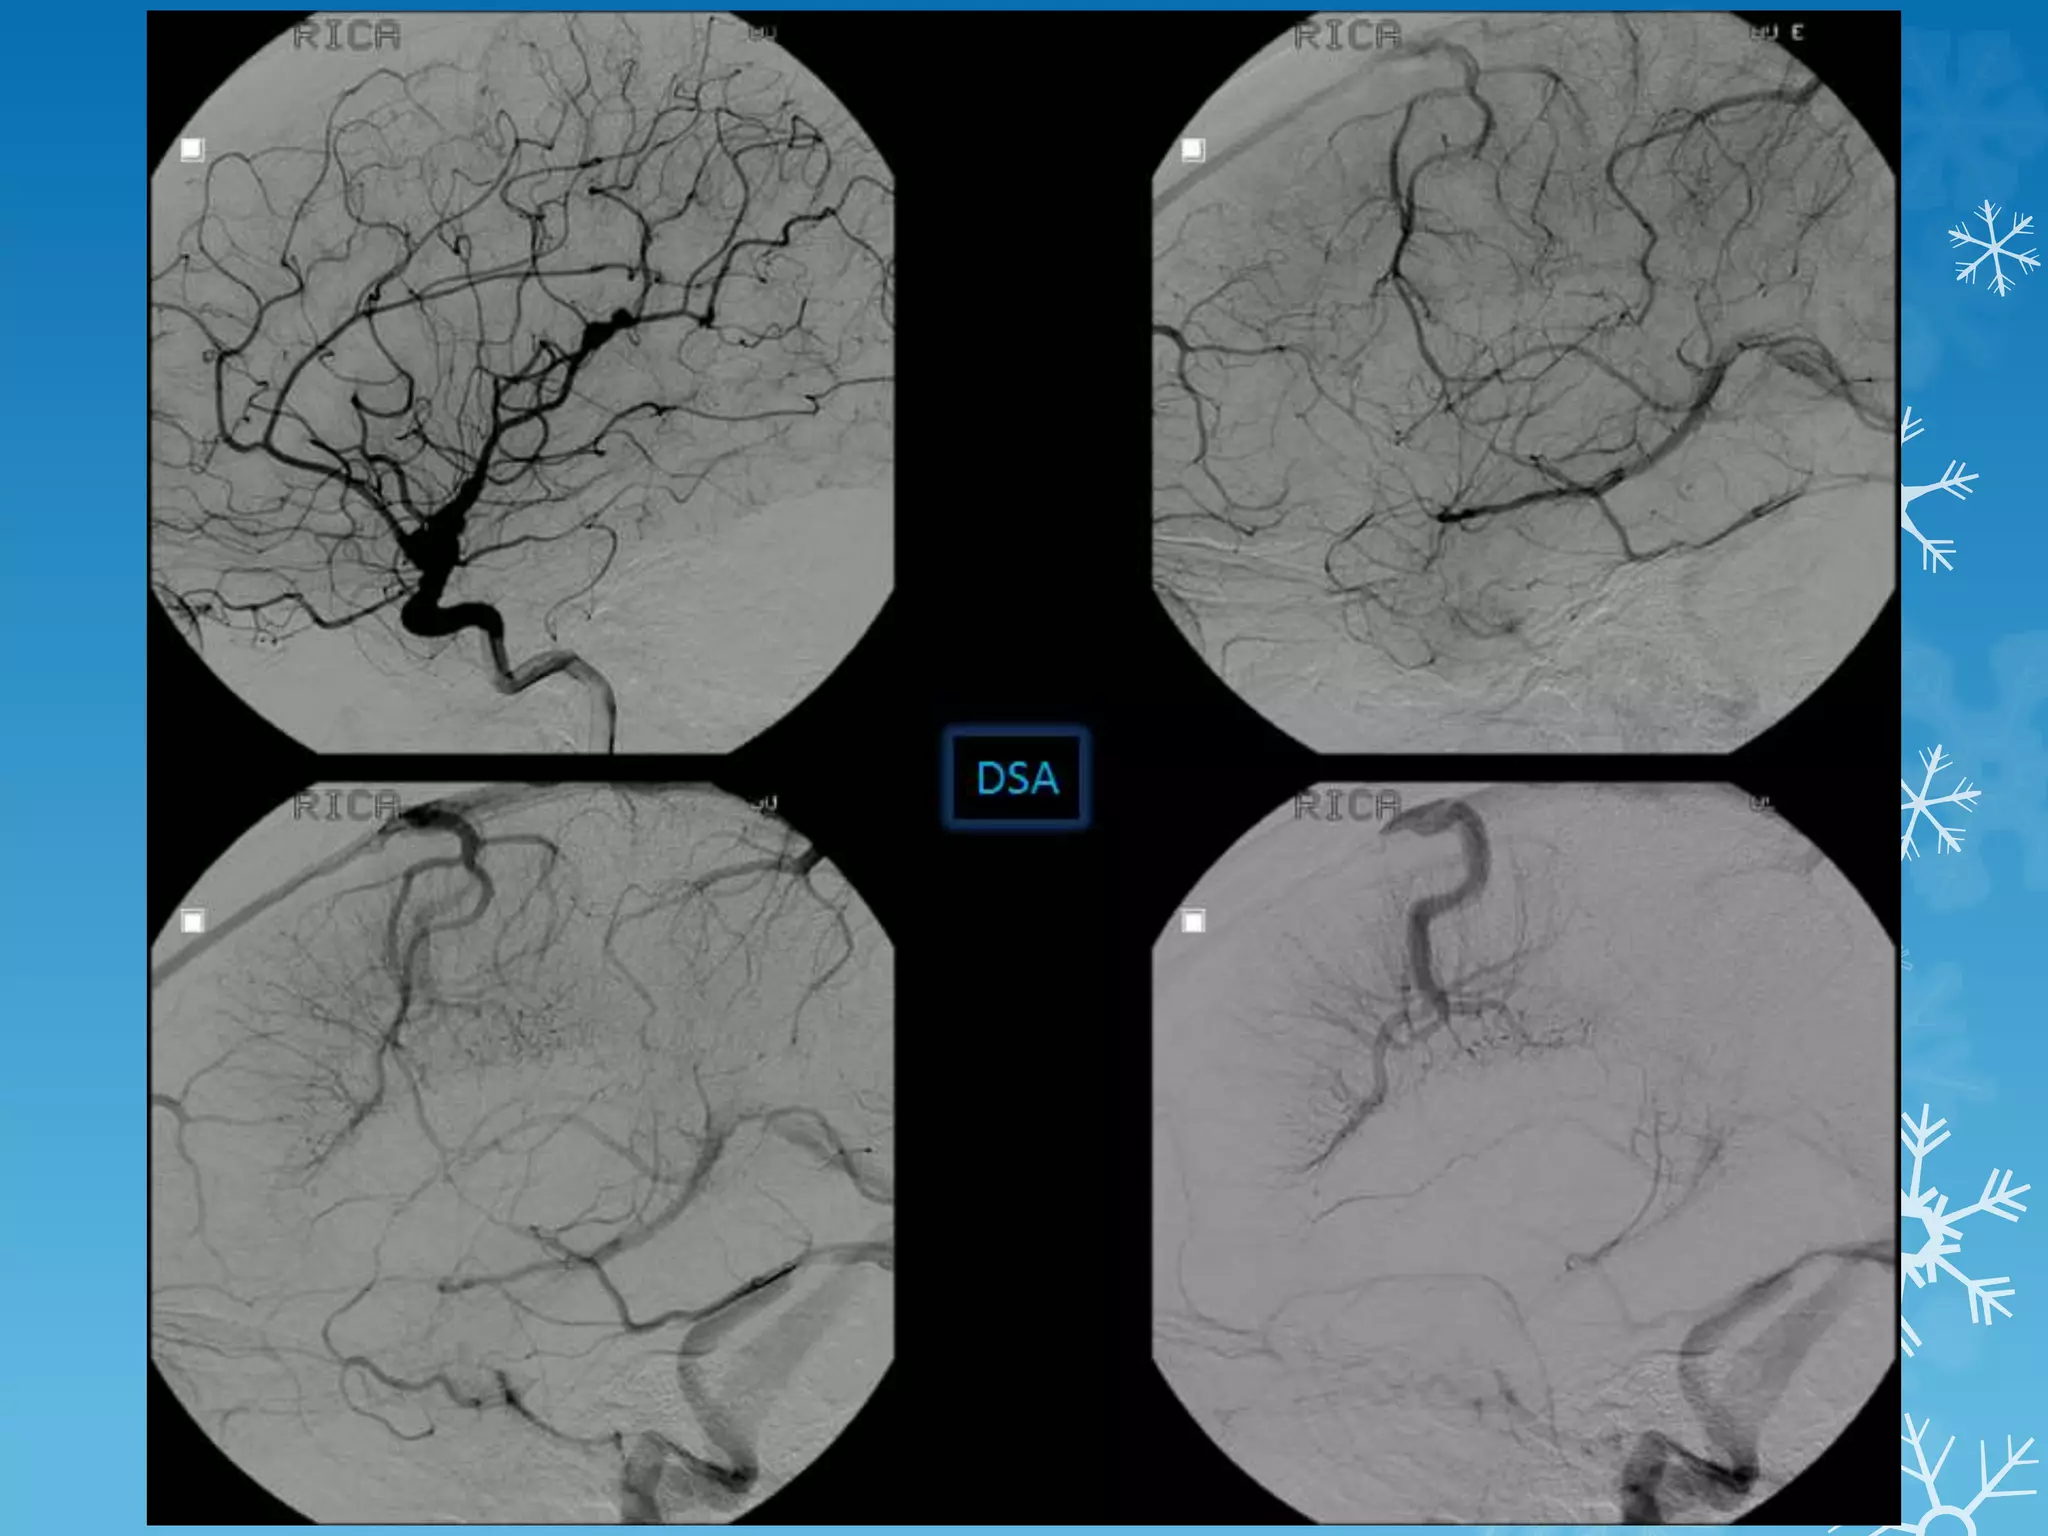

A 7-year-old boy presents with repeated transient ischemic attacks.

Moyamoya Disease